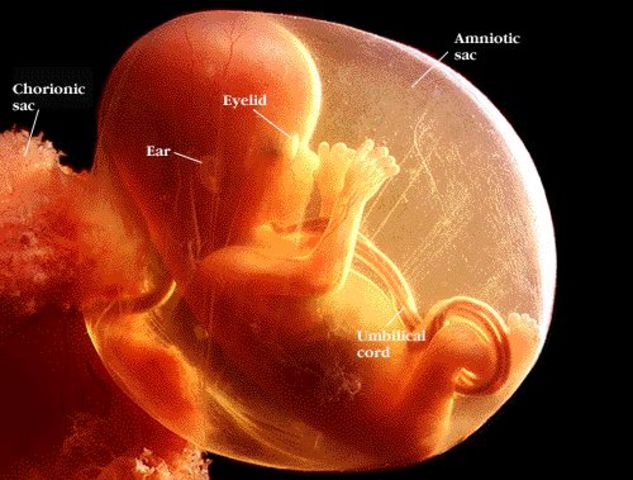

• fetal stage

fetal stage

by the start of the fetal stage all the basic organs and parts except the sex organs will have been formed at this point. this is just about the body continuing to develope and get stonger. this period goes until the ninth week till birth.

• the fetus

the fetus

the early body systems and structures continue to develope. the sex organs being to appear. the fetus grows in length and weight, the magority of the physical growth occures in the later stages of the pregnancy, this domain is physical

• fetal growth

fetal growth

this stage is marked by amazing change and growth. during the third month gestation, the sex organs began to differentaite and by the end of the month all the parts of the body will be formed, at this point the baby weighs about three ounces, this domain is physical..